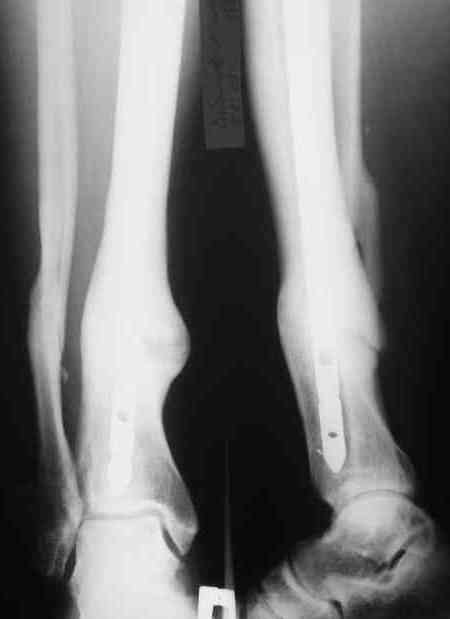

Год назад на форуме обсуждался случай не совсем удачного интрамедуллярного синтеза большеберцовой кости. Номер в архиве 3392 от 27.10.07. Были предложены различные алгоритмы оперативного лечения. Больной от повторной операции отказался. сейчас полная функция, полная консолидация, занимается спортом.

Похоже все-таки, винты, которые не проходили через отверстие в штифте, а выполняли роль "поллеров" (введеных диаметрально неправильно), были удалены? Природа взяла свое, не смотря , ни на что. И даже ось получше стала (хорошо, что винты убрали, они мешали).

Можно поздравить всех причастных! К счастью, хотя бы иногда природа исправляет наши ошибки и недоделки.